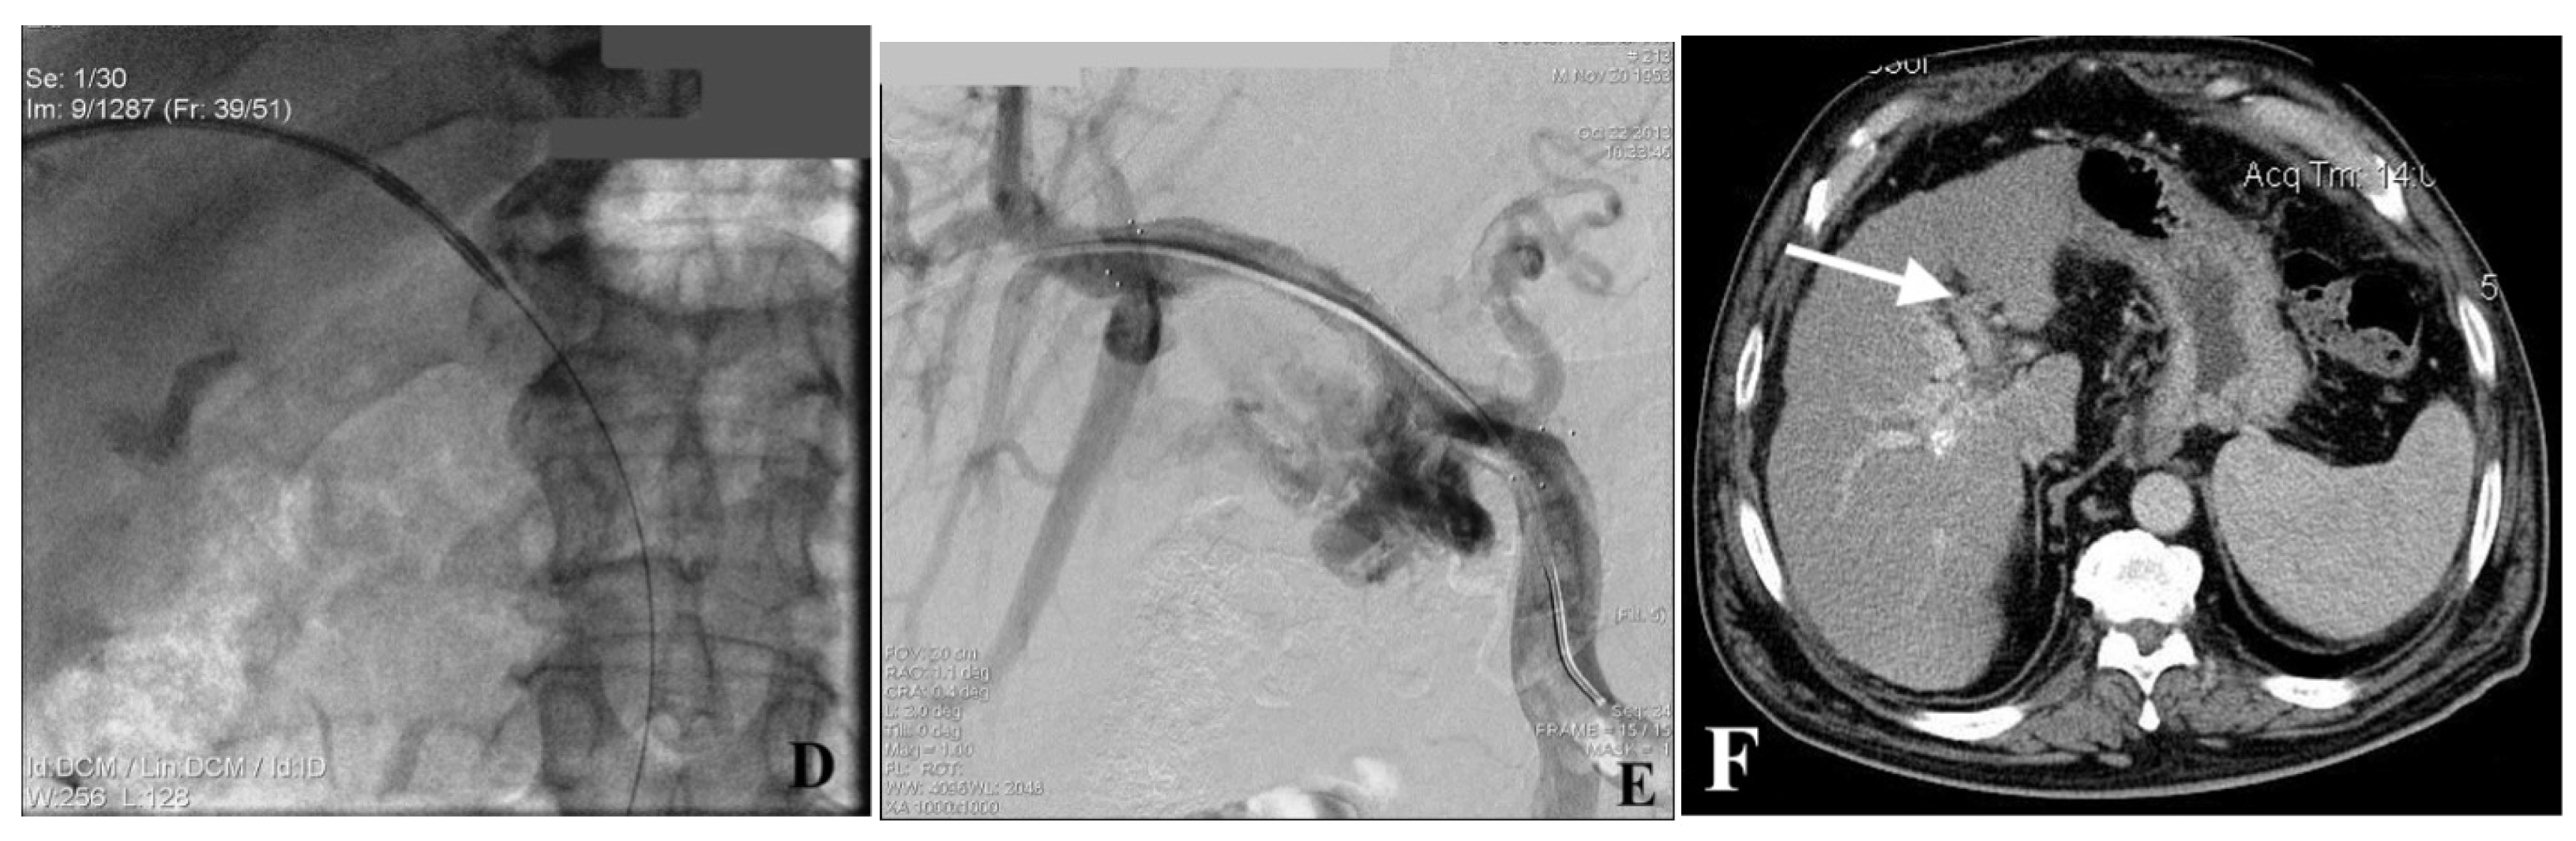

2.4. Portal Vein Access, Venogram, and Recanalization (PVR)

2.5. Endoportal Radiofrequency Ablation

2.6. Portal Vein Stent Placement